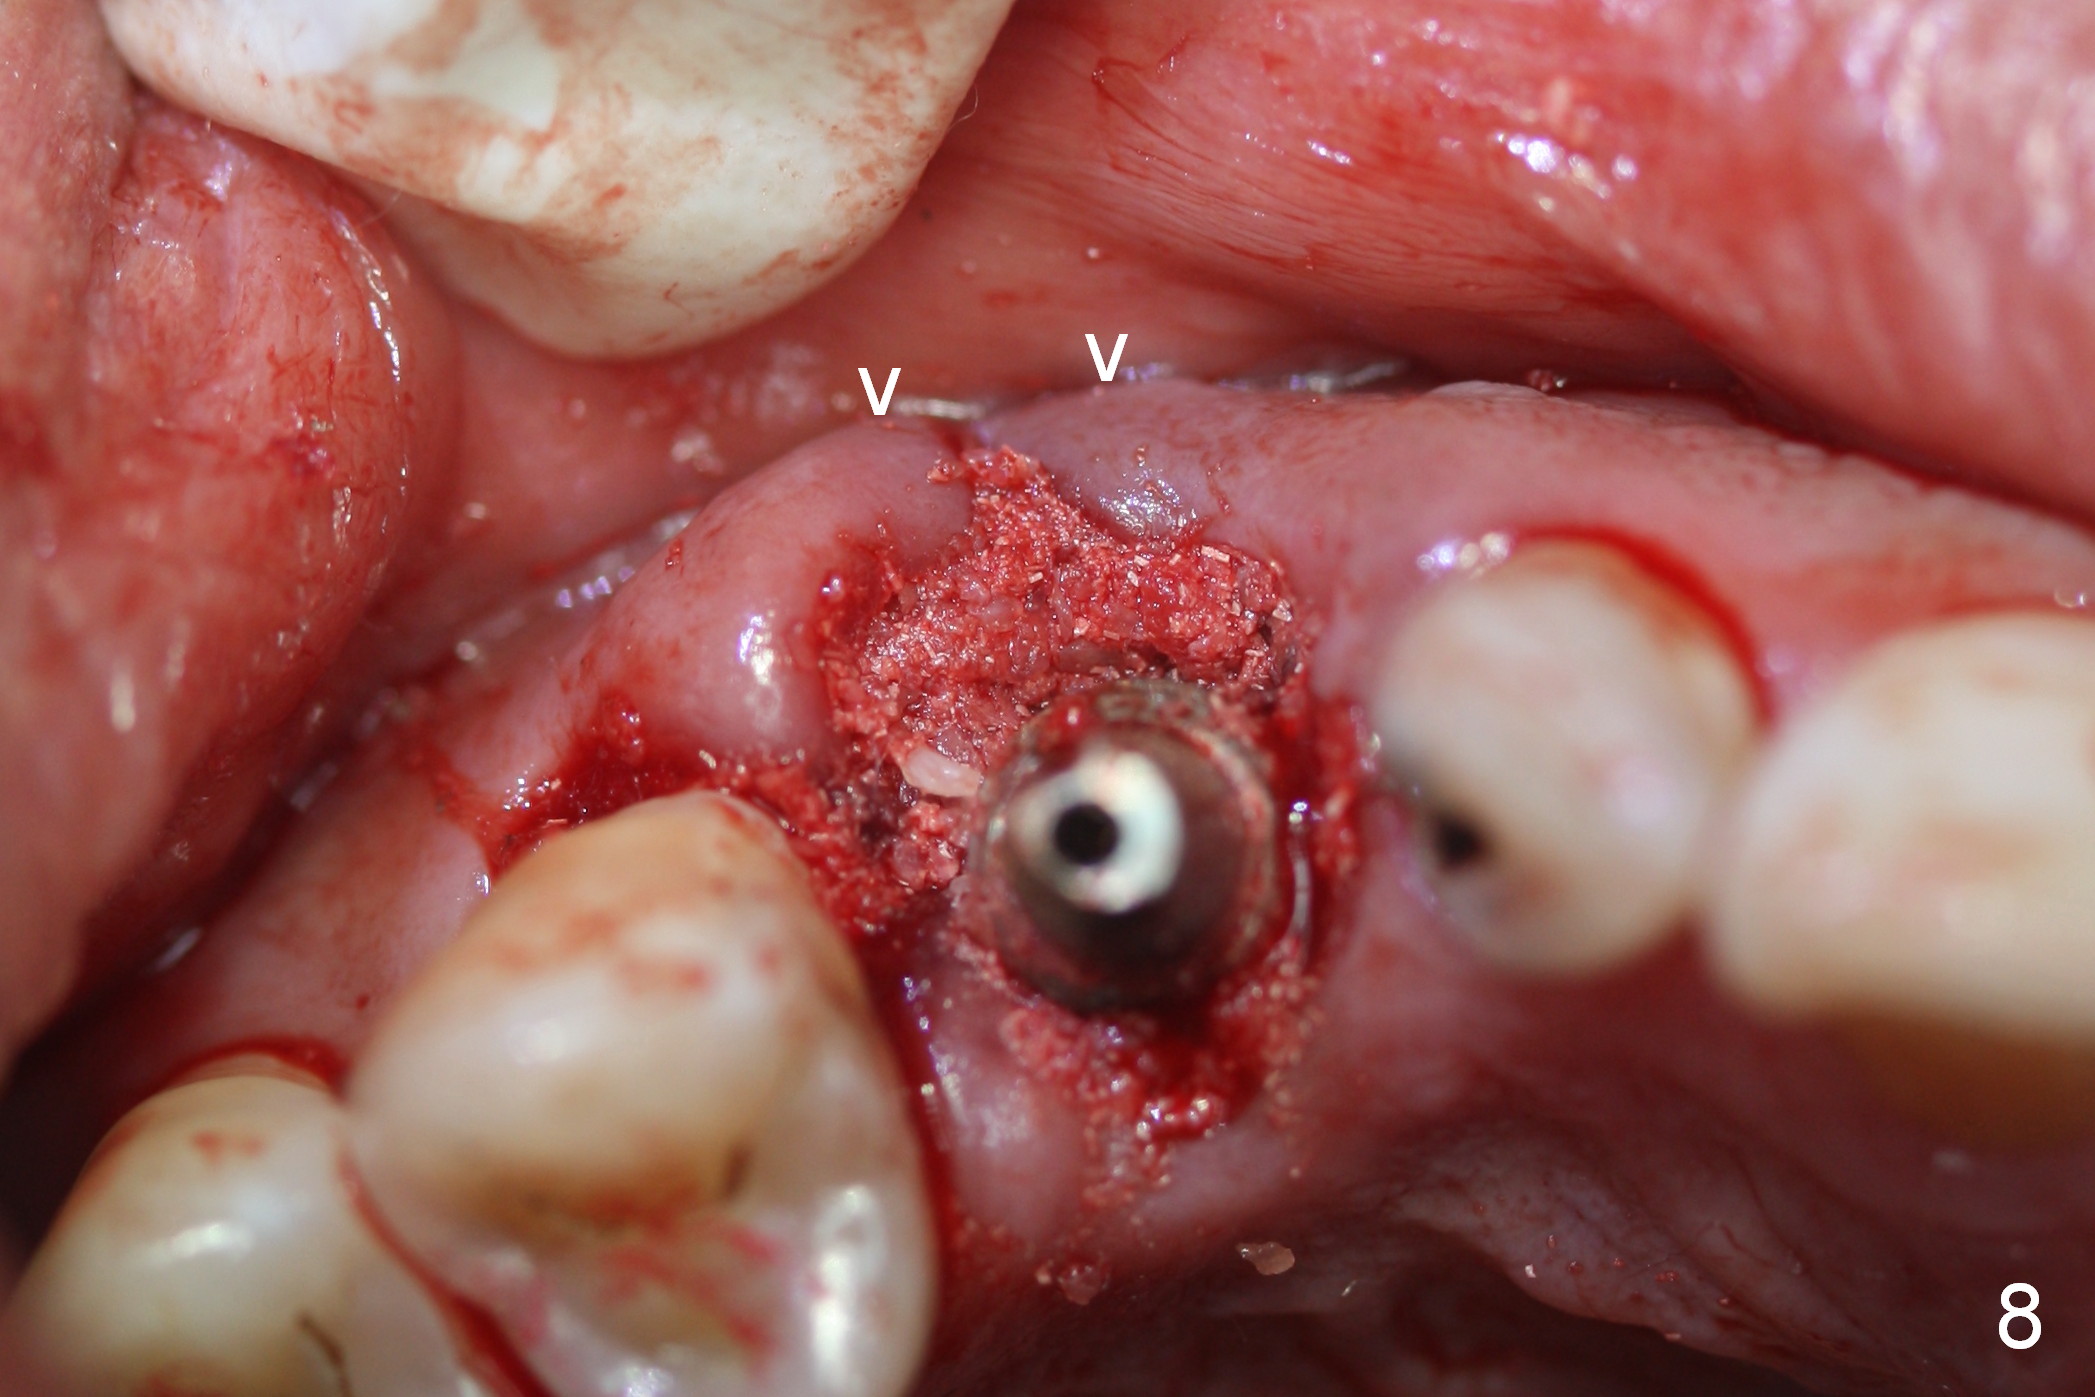

After 5x20 mm implant is placed, the distal gap is filled with bone graft (Fig.5 *). An abutment is placed (A) for fabrication of an immediate provisional (Fig.6 P). The latter hold the labial gingiva bulging (Fig.6 >). When the provisional is removed for bone grafting, the labial gingiva collapses (Fig.7 arrowheads). In fact a piece of cone-shaped Osteotape (Impladent) is placed palatal to the labial gingiva/thin labial plate and a small amount of graft is placed in the deepest area of the socket (labial to the osteotomy) prior to placement of the implant. More graft is placed in the peri-implant gap, particularly labially to keep the labial gingiva convex (Fig.8 arrowheads). The lacerated gingiva is to be approximated with perio glue (Fig.9 <). Collagen dressing is placed over the exposed graft before cementation of the provisional. Perio dressing is applied for further protection and seal.